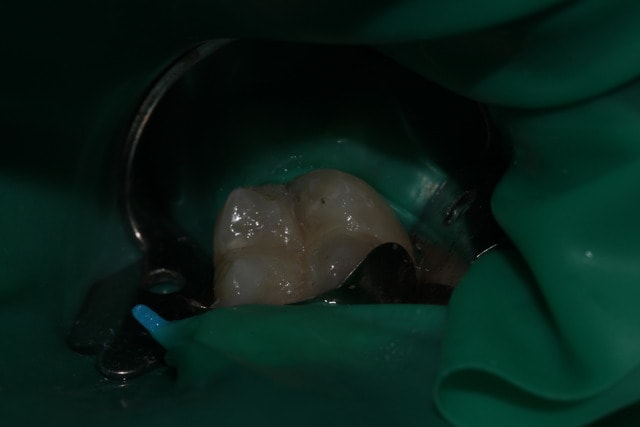

Il a été suggéré que je bossais à la zob. J'ai donc pris des photos des quelques boulots de l'aprem.

Rien de très intéressant, mais je crois avoir déjà posté un certain nombre de cas ici, tous critiquables mais aucun bâclé.

Pour ceux qui n'ont que ça à foutre, vous pouvez les relier aux posts précédents.